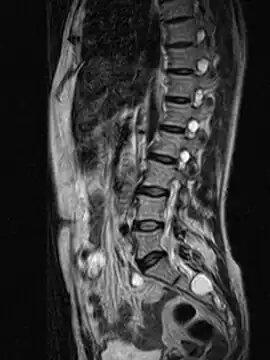

MRI image showing a Tarlov cyst -

MRI sagittal image of sacral and dorso-lumbar perineural cysts.

MRI

MRI, or Magnetic Resonance Imaging, is considered the imaging study of choice in identifying Tarlov cysts. MRI provides better resolution of tissue density, absence of bone interference, multiplanar capabilities, and is noninvasive. Plain films may show bony erosion of the spinal canal or of the sacral foramina. On MRI pictures, the signal is the same as the CSF one.